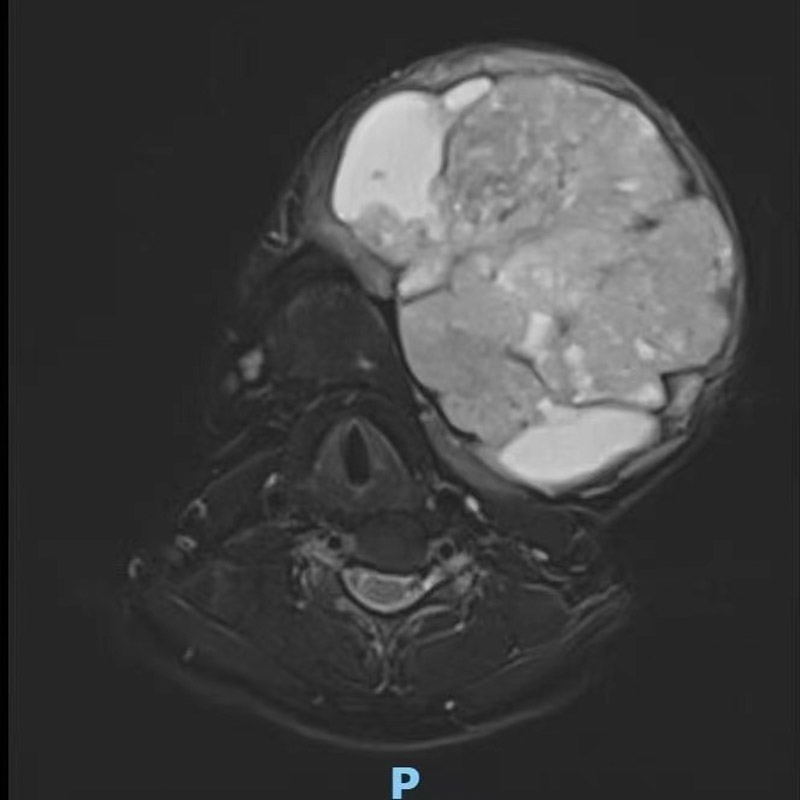

無奈之下,近日,劉女士在家人的陪同下來到了柳州市人民醫院口腔科就診。接診的副主任醫師劉彥杰看到患者情況后也有些吃驚,這是他從醫多年見過的最大的下頜骨腫瘤。經檢查發現,腫瘤已經完全侵犯患者左邊下頜骨,口腔內還有一大塊腫瘤暴露,左下牙已經完全被腫瘤侵犯消失,腫瘤很容易出血,上頜骨也被腫瘤壓迫變形。好在腫瘤表面皮膚還比較完整,可以用來做術后口腔缺損的修復。

患者入院后活檢結果為成釉細胞瘤,成釉細胞瘤是常見的牙源性上皮性良性腫瘤之一,又稱造釉細胞瘤,該病初期發展緩慢,無自覺癥狀。逐漸發展可使頜骨膨大,造成畸形,左右面部不對稱。腫瘤侵犯牙槽骨時,會使牙松動、移位或脫落;腫瘤繼續增大,會使頜骨外骨板變薄,甚至吸收,這時腫瘤可以入侵軟組織;當腫瘤壓迫下牙槽神經,患側下唇及頰部可能感覺麻木不適;如腫瘤發展很大,骨質破壞較多,會發生病理性骨折。

口腔科立即在科內開展了病例討論,考慮到患者下頜腫塊異常巨大,再結合其經濟狀況,首要治療就是先切除腫瘤,二期手術再進行下頜骨的修復重建。該手術的難點主要體現在兩方面:第一是精準切除腫瘤,需要腫瘤切除醫生團隊積累沉淀豐富手術經驗,才能把腫瘤完整切除;第二是對缺損部位進行外形、功能的精確修復,這一步相對更難、更復雜。